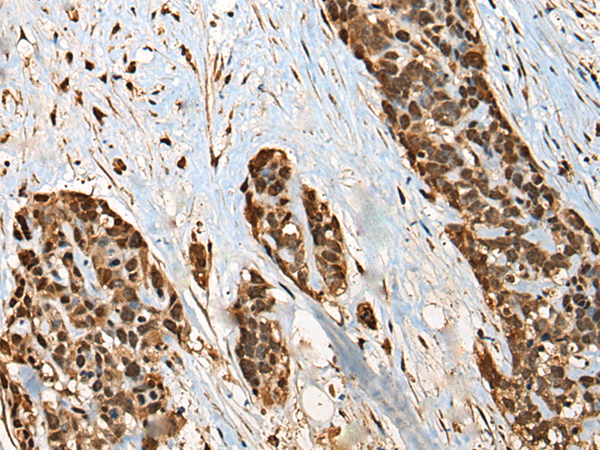

分类: 科研抗体货号: P09449别名: HEI10; C14orf18应用: WB,IHC反应种属: Human, Mouse